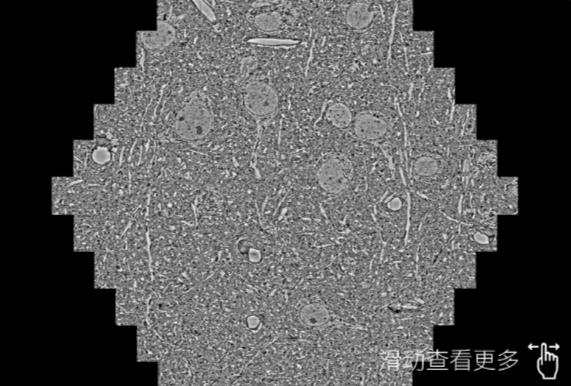

鼠脑切片。左图使用东城蔡司东城扫描电镜MultiSEM706对165μmx143pm面积区域成像,耗时仅需1.5秒。右图为鼠脑切片中30μm区域放大效果。样品由芝加哥大学B.Kasthuri提供。

使用蔡司高速东城扫描电镜MultiSEM对1mm²人脑皮层组织进行高分辨成像,并对其中的各种细胞结构进行三维重构分析。左图展示了2x3mm²组织平面中锥体神经元的三维重构效果。右图显示了局部体积神经元三维重构。图像由哈佛大学chtman实验室提供,渲染图由D. Berger 制作。